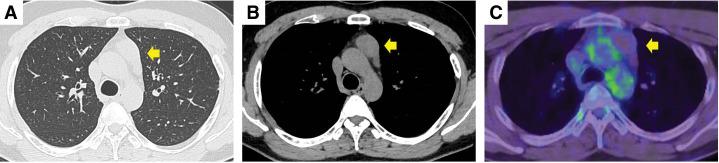

一名30岁男性因健康检查时发现短暂性胸痛和纵隔肿块被转诊至我院。正电子发射断层扫描/计算机断层扫描显示无氟脱氧葡萄糖摄取,血清和生化分析显示炎症反应或肿瘤标志物水平未升高。根据影像学检查结果,胸腺囊肿和胸腺瘤被列为鉴别诊断,遂行胸腔镜纵隔肿瘤切除术。通过增厚的胸膜与肺粘连的包膜肿瘤被成功切除,并快速诊断为胸腺瘤。最终病理检查证实为B2型胸腺瘤,坏死约占肿瘤的80%。患者一直在门诊随访,术后1年无复发。